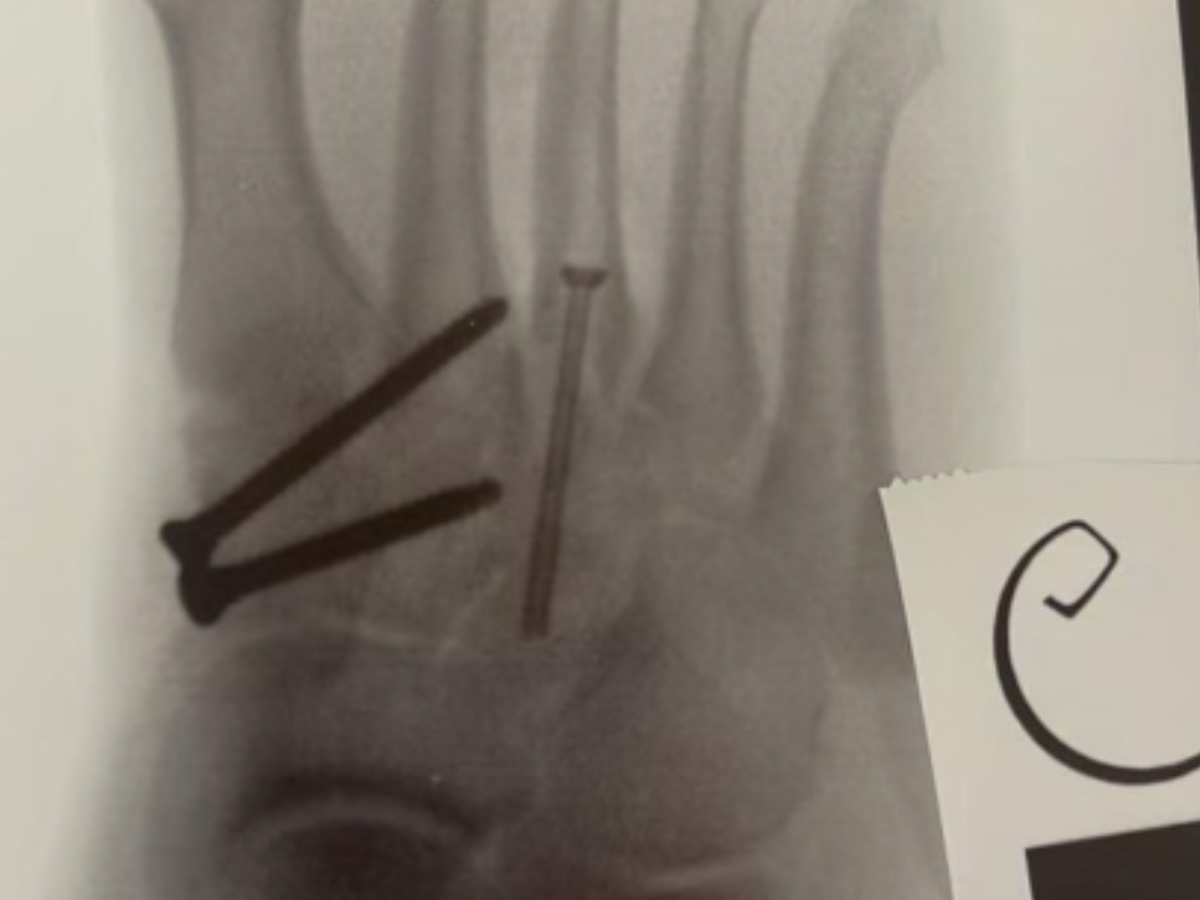

UPDATE: Back in December Leah broke her foot NFL style, and snapped three bones across her right foot. One of those bones is the supporting bone which she needed surgery, otherwise any weight would cause her foot to cave in and create irreparable damage and possibly a disability.

She had a necessary surgery on Monday 22nd January which went well, and although she can start to bear a little weight on it, she can only put about 80% weight on it in about 2-3 months, so she is still relying on her knee scooter and crutches to get around to which she would be completely immobile without them.